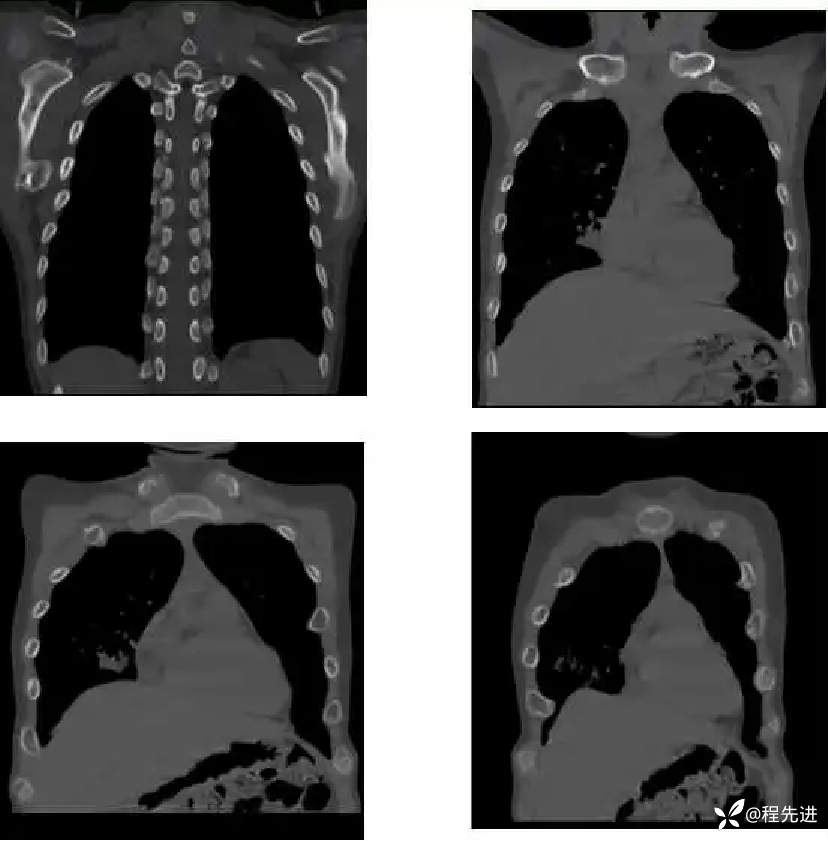

患者性别:男

患者年龄:11岁

简要病史:受凉后发热3天

既往史:生长发育迟缓

胸部CT: